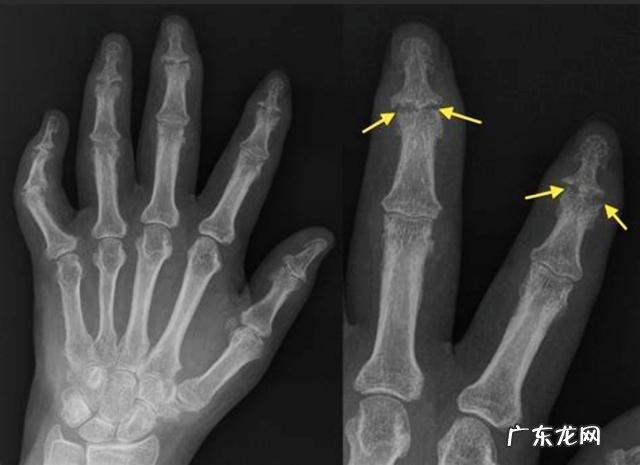

另外当患者患有骨关节炎的时候 , 早期会在手指的远端有一些特殊的改变 , 在患者的手指远端关节处会出现一些小的结节 , 触碰会有疼痛感 , 但如果不过度触碰是没有任何感觉的 , 在早期的时候甚至拍片子也发现不了明显的骨关节改变 , 这种情况 , 我们称之赫伯登结节 , 往往预示着患者身体存在着骨关节炎 , 也预示着手部将要出现比较明显的骨关节炎改变 。

诊断:如果存在着手部僵硬、疼痛 , 活动受限 , 出现了赫伯登结节 , 那么应该高度可疑存在着骨关节炎 , 诊断往往要进行手部的x线检查 , 可以发现手指关节间隙的狭窄 , 可以发现轻度的骨质增生或者是严重的骨质增生 。也可以进行风湿4项化验 , 排除是否存在着痛风、风湿病或者是类风湿相关疾病 。